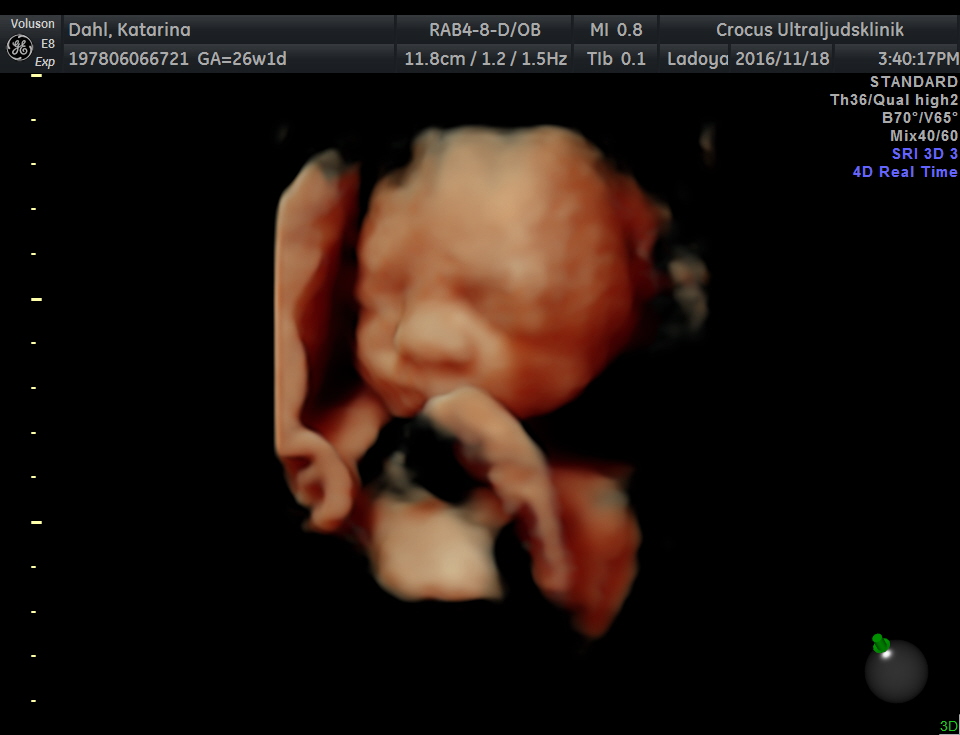

Gravid ett annorlunda nöje

Fick veta på min födelsedag att jag var gravid.

Lite ställd o reagerade nog inte helt efter förväntningar från gyn läkaren.

Men efter lite tid kom glädjen för både mig o min man.

Sen kom kräkningarna ända fram till v 20

Sen hade jag hela 4 veckor där jag mådde bra, äntligen 👍😀💕

4 veckor sen började det om kräks o ont i magen, bukspottkörtelinflammation konstaterade dem. Gallan var också inflammerad. Hju pendla mellan inlagd o hemma. Men mest inlagd skulle jag tro..

3 veckor kvar gav dem med sig o plockade ut våran lilla Milo.

Milo 3/2

Milo